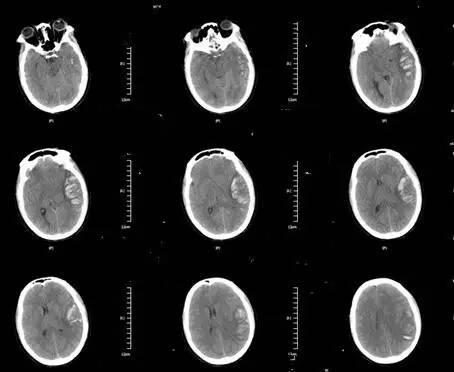

基本信息:患者女性,46岁。因“突发神志不清伴有右侧肢体无力1天”,2015-12-23入院,神志昏睡状,GCS评分3+1+5=9分,左侧瞳孔4mm、对光不明显,右侧孔2密码、,对光迟钝,左侧肢体刺痛定位,右侧肢体无活动。

▼头颅CT提示:左侧颞顶叶血肿。

诊治经过:考虑存脑疝,予开颅血肿清除+去骨瓣减压术,,术后予降颅压对症治疗。考虑患者可能存颅内静脉窦血栓,行MRV及全颈脑血管造影术,示“左侧横窦闭塞 矢状窦、右侧横窦血栓形成”。予华法林抗凝治疗。出院PT-INR:2.11。门诊随访中。